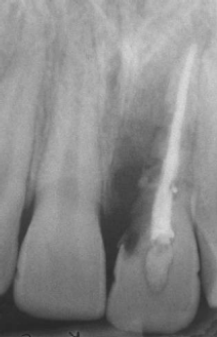

Analise a radiografia periapical a seguir:

Assinale a alternativa que corresponde corretamente à condição apresentada pelo elemento dental 21.